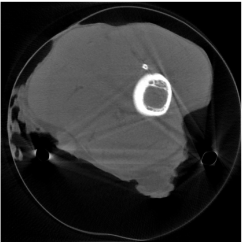

where is the restriction operator with respect to the domain . The restriction operator is defined as: for ; and for . The optimization problem (2.13) can be solved similar to (2.12) by the split Bregman algorithm. We denote the solution of (2.13) as (Figure 2(a)).

The weights will be computed by projecting a segmented image that approximates tissue classification of the unknown CT image. One may obtain such approximated tissue classification by segmenting image obtained from (2.12) or obtained from (2.13). However, the approximation from either image will be rather inaccurate since has severe artifacts in between metal locations (Figure 1(b)), while the metal components are missing from (Figure 2(a)) though there are less artifacts in between metal locations. Therefore, we propose to segment a combined image defined by

with a tuning parameter. In this paper, the segmentation of is obtained by the algorithm proposed by [34, 35]. The segmented image, denoted as (Figure 2(b)), contains three components: the air, the low density components such as soft tissues, and the high density components such as bones and metals. The intensity values of the segmented image from prior image are assumed to be constant for each segmented component. We propose to use the mean values of in the segmented regions as the constants. After obtaining , the weight that will be used in our re-weighted JSR model is defined by . Finally, we note that the reconstructed image using the re-weighted JSR model is relatively insensitive to the choice of the parameter in (2.14), which is demonstrated in Table 2 using NCAT phantom.